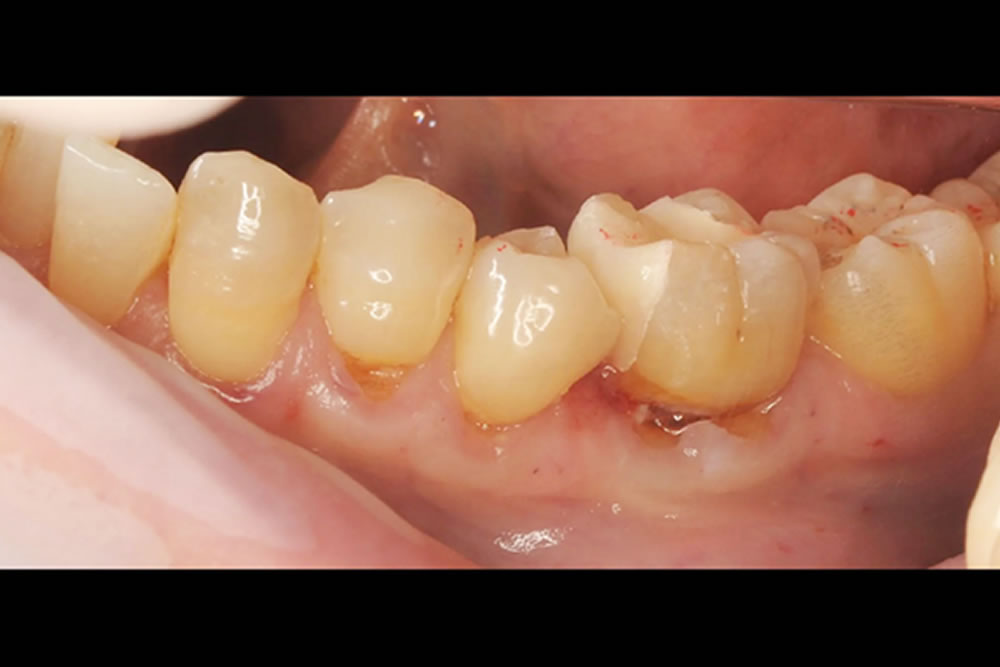

下がった歯茎をマイクロスコープ精密治療・根面被覆術で改善した症例

| 主訴 | 歯がしみる |

| 治療内容 | ・根面被覆術 ・マイクロサージェリー |